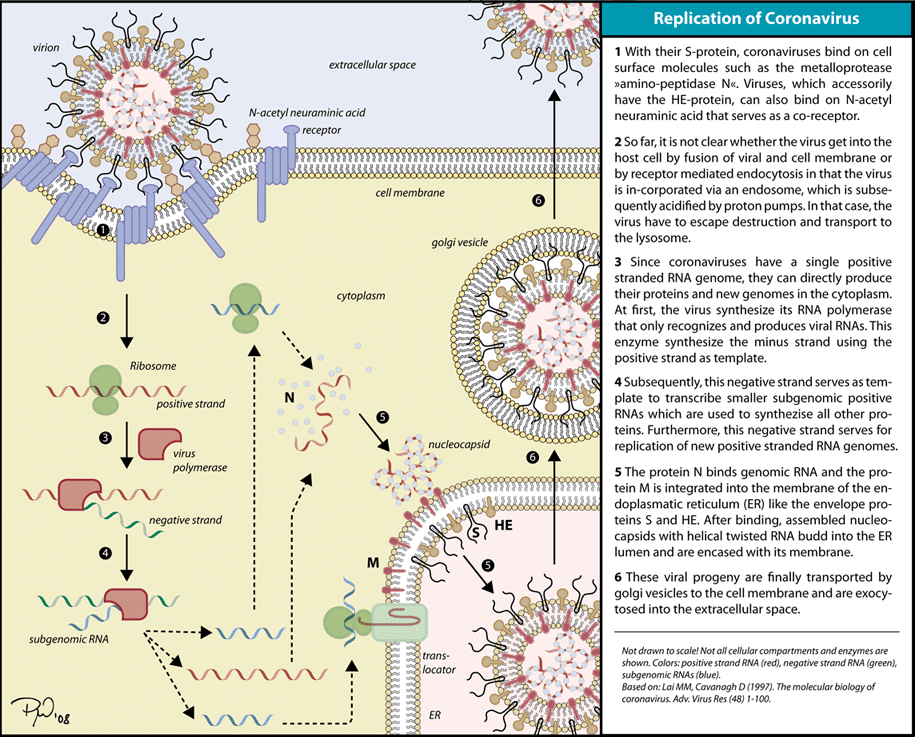

Trước khi bùng phát dịch COVID-19, một nghiên cứu tiến hành trong tự nhiên công bố năm 2015 đã cảnh báo nguy cơ tiềm tàng tái phát dịch SARS-CoV, dựa trên các chủng virus tồn tại trong quần thể dơi Trung Quốc. Dựa trên nguyên lý kỹ thuật di truyền ngược mã gen SARS-CoV, một nhóm nghiên cứu tên là Ralph Baric đã tạo ra và miêu tả tính chất của coronavirus SHC014, một loại virus chimera có protein gai (protein S, spike protein) lấy từ chủng SARS-CoV đã thích nghi với chuột. Việc sử dụng kháng thể và vaccine đơn dòng đều thất bại trong việc vô hiệu hóa và phòng ngừa nhiễm CoV có protein gai trên bề mặt nêu trên.

Chủng virus mới gây ra các trường hợp đã được xác nhận là SARS-CoV-2 (tên gọi tạm thời là coronavirus mới (2019-nCoV)), là chủng thứ bảy trong họ coronavirus được biết đến có khả năng lây bệnh cho người, với trình tự bộ gen được báo cáo là giống đến 79,5% so với trình tự bộ gen của SARS-CoV và có sự tương đồng đến 96% với các chủng coronavirus lây nhiễm ở loài dơi móng ngựa.

Các nghiên cứu đã phát hiện chủng virus SARS 2 ký sinh trong người thông qua thụ thể ACE 2, giống hệt virus SARS.